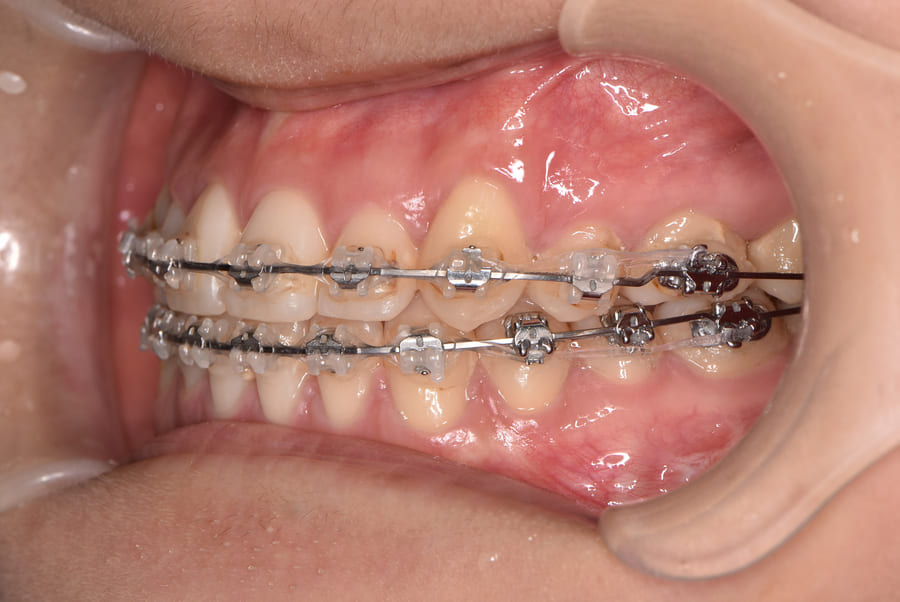

上下顎変形症に対する外科手術を併用した矯正治療《保険》

| 主訴 | 上下前歯の真ん中が合わない、かみ合わせを治したい |

|---|---|

| 診断名あるいは主な症状 | 上下顎変形症、交叉咬合 |

| 初診年齢 | 26歳 |

| 治療内容・装置 | マルチブラケット装置(上下表側からの矯正治療) 上下顎骨形成術(全身麻酔下の手術) |

| 抜歯・非抜歯 | 上下顎左右智歯抜歯 |

| 治療期間 | 1年7か月 |

| 費用 | 140,000円(保険適用、当院での自己負担額) |

| 治療のリスク | 歯の移動に伴う痛み 上下顎前歯部の歯根吸収 装置による口内炎 ブラッシング不良によるむし歯、歯周炎 外科手術後の痛み、腫れ、知覚鈍麻 |